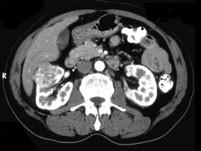

问题 男,56岁,无痛性全程血尿1个月,CT平扫及增强检查如图,下列说法正确的是 ( )

选项 A、右肾静脉及下腔静脉内未见充盈缺损影 B、考虑为右肾上极的肾癌 C、增强扫描皮质期,病灶强化明显,但仍低于肾皮质的强化 D、增强扫描实质期,该灶强化迅速减退,可清楚的分辨其轮廓 E、在右肾上极,肾脏局部隆起,平扫时其密度与肾相近,不易分辨其轮廓